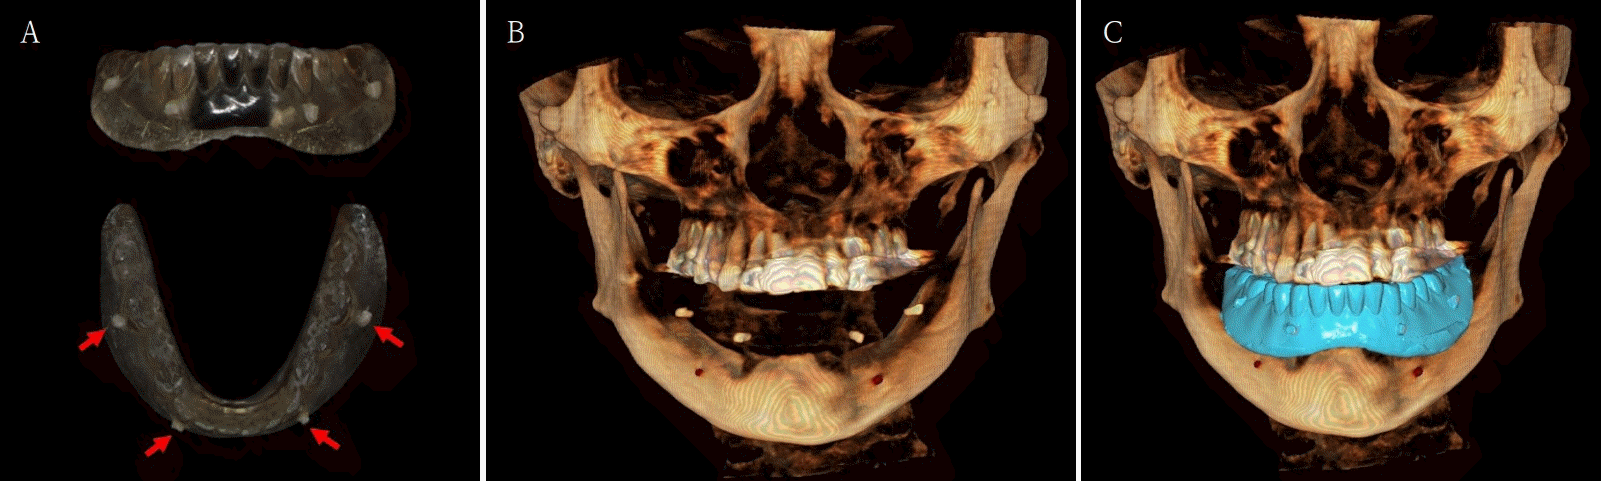

Fig. 1.

Atrophy of mandibular posterior bone is examined by pre-operative intraoral photograph. A. Maxillary occlusal view. B. Frontal view. C. Mandibular occlusal view.

Fig. 6.

A. 3-dimensional (3D) printing denture is marked with radio-opaque resin marker. B. CBCT is taken with the 3D printing denture with marker. C. Superimposition of CBCT and model scan data is completed.